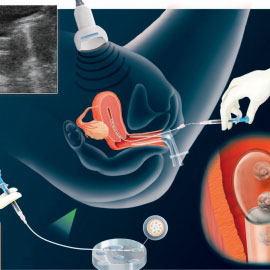

إرجاع الأجنة إلى الرحم

حيث تعاد الأجنة إلى الرحم بعد يومين إلى ثلاثة (وفي بعض الحالات بعد خمسة أيام عند الرغبة بالوصول إلى مرحلة العلقة أو الكيسة الأرومية Blastocyst) وذلك بطريقة سهلة غير مؤلمة وتتم دون الحاجة إلى تخدير إلا في حالات خاصة جدا.